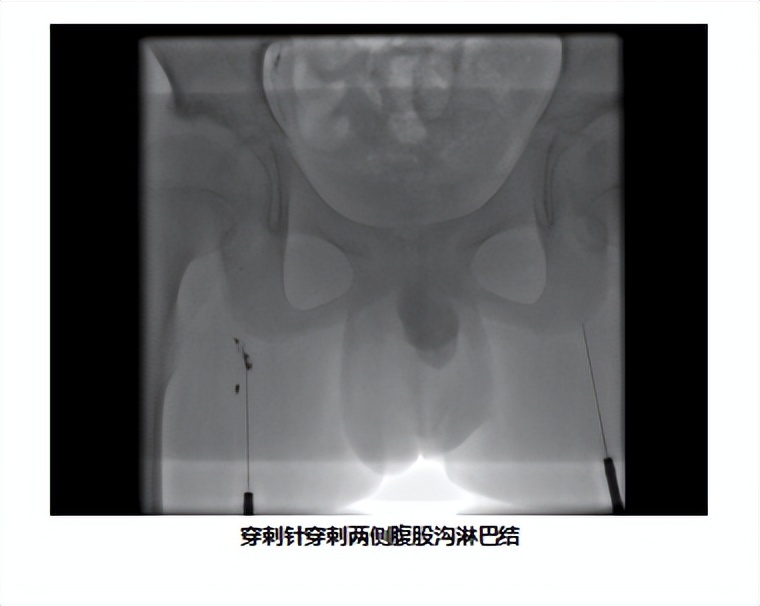

二、手术过程

在安排的手术时间,家长如约住院,顺利完成术前准备,手术当天,患儿在全麻的过程中完成了手术,耗时3小时,应用穿刺针行淋巴结穿刺,注入碘油。显示:右上纵隔淋巴管及右颈静脉角胸导管右位引流,扩张伴出口流出不畅。右侧胸腔积液,T10-12水平右肋间淋巴管造影及返流。术后孩子也没有任何不适,身上也没有任何伤疤。共住院7天,患儿平稳出院。